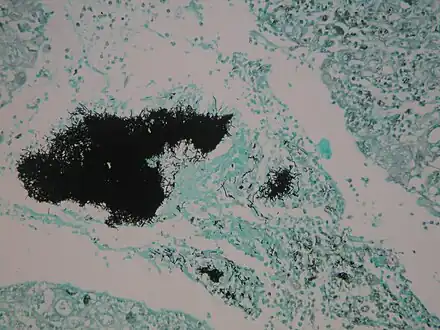

Thin Gram positive filamentous organisms seen at the periphery of the colony (upper) Actinomycosis Grocott's stain

Actinomycosis Grocott's stain Actinomycosis Gram stain